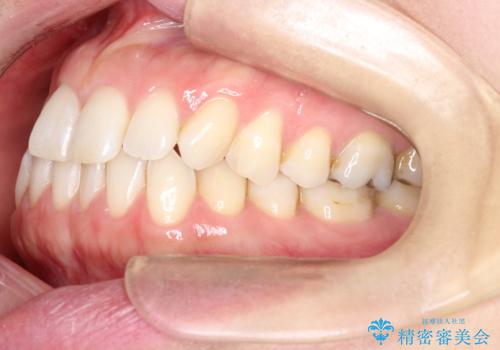

- 右上の前から2番目と3番目の歯が内側に引っ込んでしまっているのを主訴に来院されました。

右上の2番目と3番目のはが前後反対にかんでしまっている状態でした。

インビザラインにて治療することとしました。

内側に引っ込んでいる歯も、インビザラインにてしっかり外側に動かすことができます。